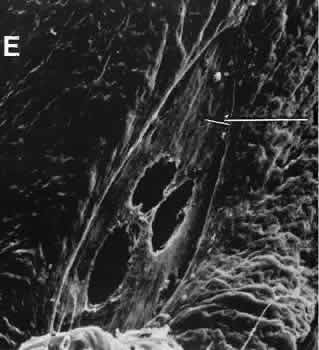

With several microkeratomes, scanning electron microscopy may show a fine undulating contour up to 0.2 mm at the border of the lamellar bed and flap. This feature is formed as chatter lines parallel to the cutting edge of the microkeratome blade (Fig. 19). The frequency of the chatter may relate to the nonlinear pass of the microkeratome. Chatter is absent in rotary keratomes and keratomes using a high oscillation frequency.66–68

Fig. 19. Scanning electron microscopy of the lamellar bed in LASIK. A. At the edge of the wound, oscillation marks caused by some types of microkeratome can be identified. B. The lamellar bed in the center of the wound is moderately irregular.